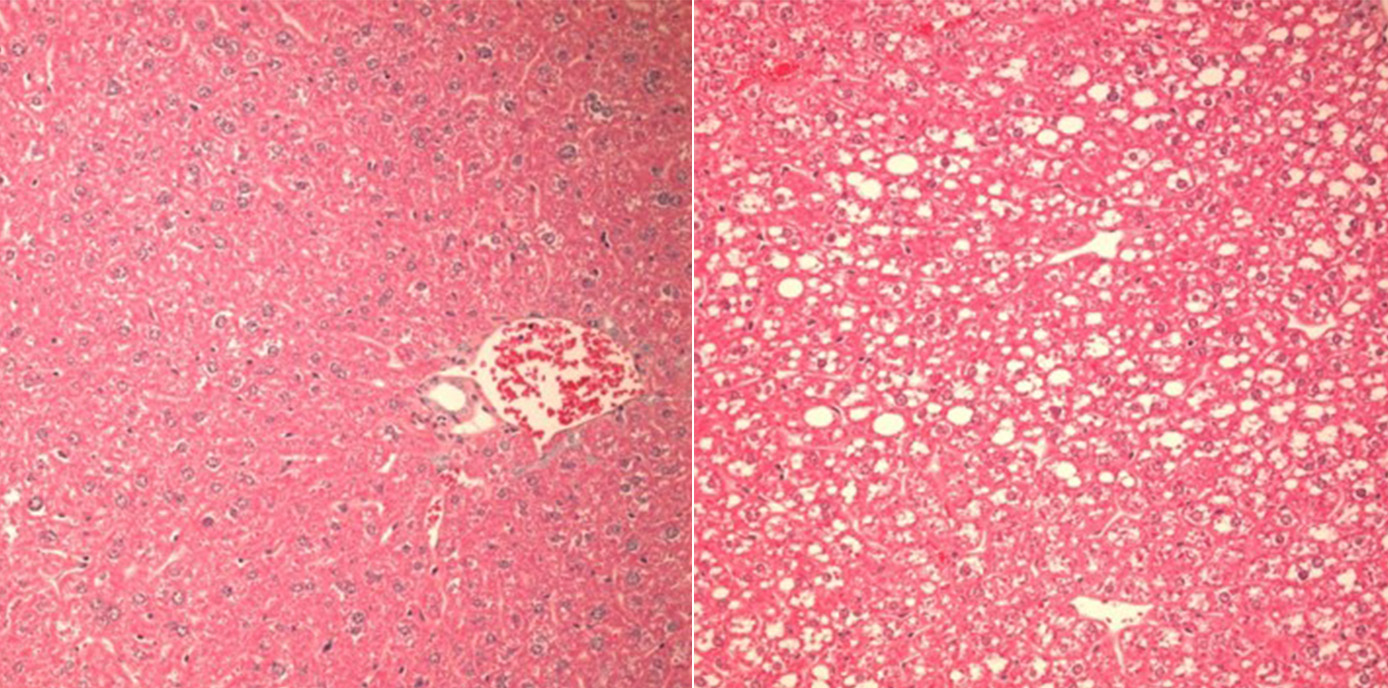

Auch wenn man noch wenig über Auslöser und Art der Caspase-2-Aktivierung in der verfettenden Leber weiß, konnten die Forscher:innen nun zeigen, dass der Verlust des PIDDosoms bei Fruktose-reicher Diät vor der Zerstörung von Leberzellen, Entzündung und Gewichtszunahme schützt. „In unseren Mausmodellen gelang es, den Einfluss des PIDDosoms auf den Lipid-Stoffwechsel und die Entwicklung hin zur Leberentzündung klar darzustellen: War Caspase-2 ausgeschaltet, entwickelten Mäuse trotz Fruktose-haltiger und Fettsäure-reicher Diät keine Leberschädigung, da die Enzyme, die sonst zur Leberverfettung führen, nicht aktiviert wurden“, beschreibt Villunger die zentrale Erkenntnis.

Die Forscher:innen belegen damit die Existenz eines bisher unerkannten Regulationssystems, das die Homöostase der Leber und die Integrität des Endoplasmatischen Retikulums stützt und so den Übergang von einer einfachen Steatose zu einer Steatohepatitis steuert, indem es den Fettsäure- und Cholesterinstoffwechsel entsprechend diätetischen Herausforderungen anpasst.